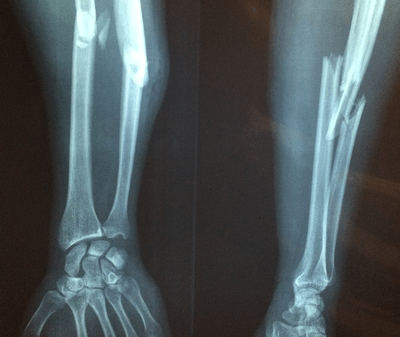

当您患有骨质疏松症时,预防骨折很重要,因为骨折会导致其他医疗问题并导致您的失去独立生活能力。 当您的医疗保健提供者根据您的个人需求定制计划时,锻炼可以帮助预防因跌倒而发生的骨折并提高骨骼强度。 如果您患有骨质疏松症或骨质流失,请务必在开始任何锻炼计划之前咨询您的医生或物理治疗师。 此外,防止跌倒有助于防止骨折。 跌倒会增加髋部、手腕、脊柱或骨骼其他部位骨折的可能性。 采取措施防止在屋内和屋外跌倒有助于预防骨折。